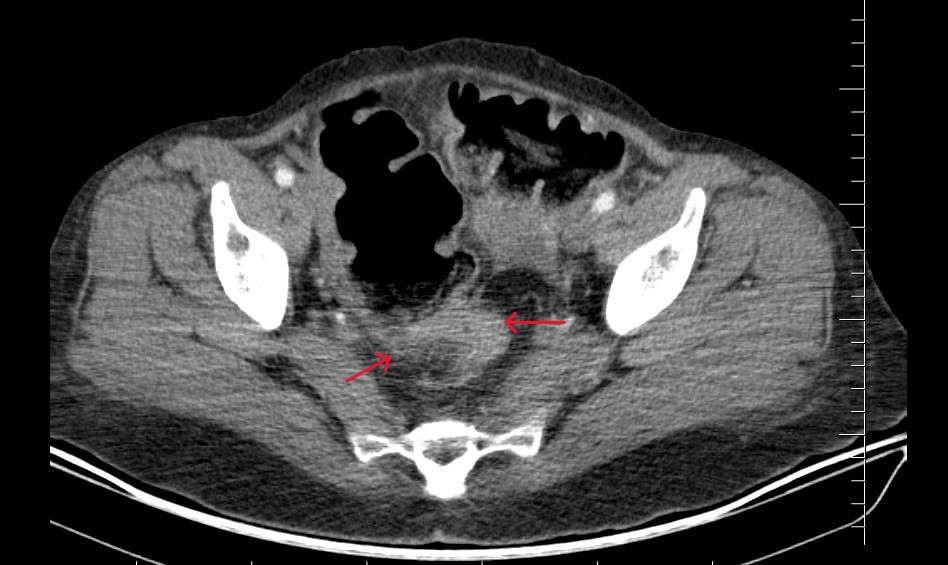

Karın ağrısı ve uzun süredir devam eden kabızlık şikâyetiyle hastaneye başvuran hastaya yapılan detaylı tetkikler sonucunda rektum kanseri tanısı konuldu. Genel Cerrahi Uzmanları Op. Dr. Hanifi Furkan Yıldız ve Op. Dr. Muhammed Furkan Karadoğan tarafından gerçekleştirilen ameliyat, kanser cerrahisi prensiplerine uygun şekilde başarıyla tamamlandı.